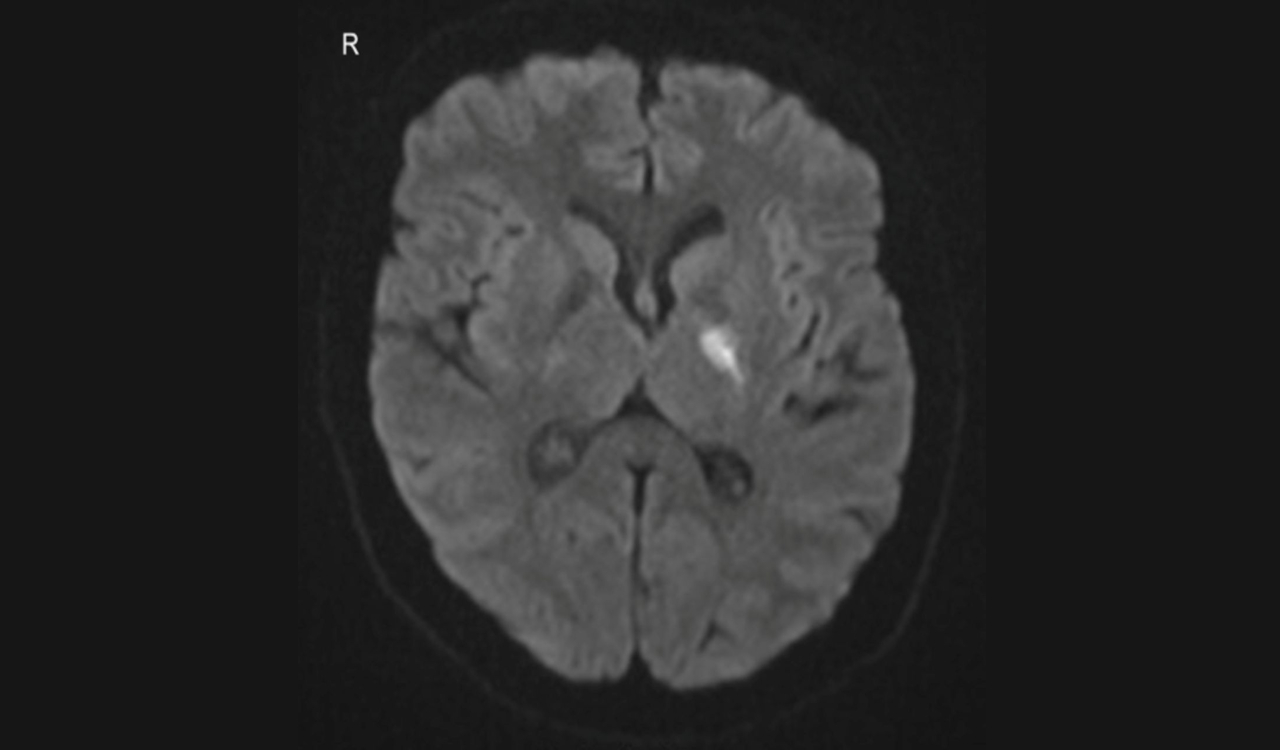

Світла пляма позначає відмерлі внаслідок інсульту нервові клітини в мозку жінки. Lai & Ratnayake / BMJ Case Reports, 2025

Але після ангіографії, тобто сканування судин, і повторного перегляду знімків комп’ютерної томографії лікарі виявили, що в пацієнтки від народження не було цієї артерії. На це вказав недорозвинений канал лівої сонної артерії у скроневій кістці. На знімках комп’ютерної томографії в жінки виявили лакунарний інсульт — відмирання нервових клітин у невеликій ділянці в глибинних структурах мозку. Позаяк у пацієнтки не було порушень мозкового кровообігу, попри відсутність внутрішньої сонної артерії, як і факторів ризику інсульту, таких як шкідливі звички та високий рівень холестерину в крові, то причиною інсульту назвали хворобу малих судин невідомого походження.